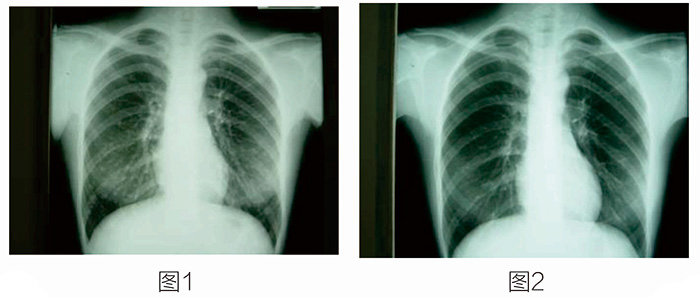

放射性核素治療開展得最早、應(yīng)用得最廣泛的就是碘-131治療甲狀腺癌及其轉(zhuǎn)移灶,其它項(xiàng)目還有放射性核素治療癌癥骨轉(zhuǎn)移等。 這是一位34歲的女性,有甲狀腺乳頭狀腺癌。圖1示雙肺多發(fā)轉(zhuǎn)移。圖2是口服碘-131治療七次后,雙肺轉(zhuǎn)移灶完全消失。